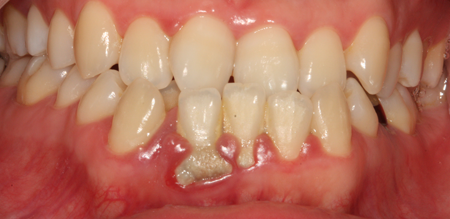

치주염 (중기~말기)

주기적으로 잇몸이 붓고 피가 나며, 욱씬하거나 우리한 통증이 나타남.

치주치료 및 정도에 따라 치주수술(잇몸수술)이 필요함. 향후 관리 정도에 따라 3~6개월 간격으로 내원하여 유지치료를 시행하여야 함.

치주염 (말기)

잇몸이 항상 부어 있으며, 이가

흔들리는 정도가 점점 심해짐.

치주치료가 필요하며, 정도에 따라 치아를 발치하여야 할 수 있음.

치주치료 전후사진

B

A